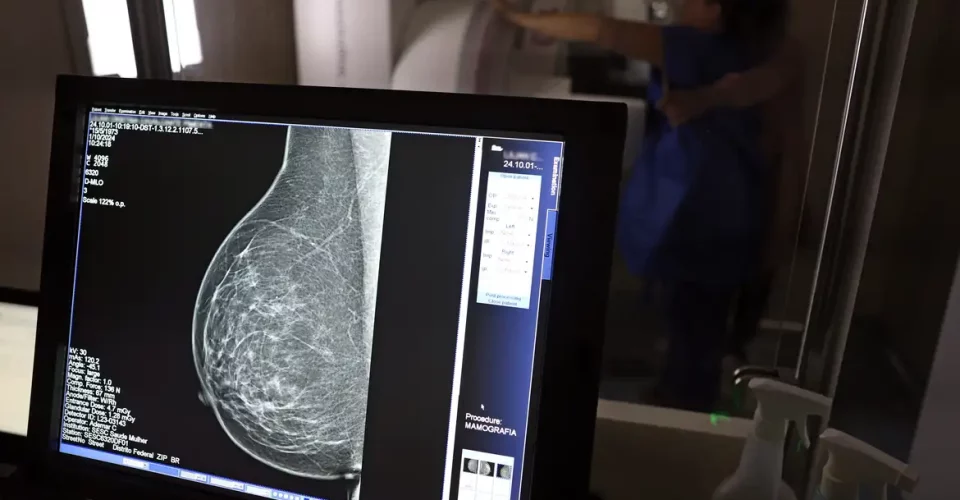

Dados do Painel Oncologia Brasil, analisados pelo Colégio Brasileiro de Radiologia e Diagnóstico por Imagem (CBR), indicam que mais de 108 mil mulheres com menos de 50 anos foram diagnosticadas com câncer de mama no Brasil no período entre 2018 e 2023 – uma média de uma em três mulheres diagnosticadas com a doença.

Para a entidade, os números reforçam a importância de ampliar o rastreamento do câncer de mama por meio da realização de mamografia em mulheres abaixo dos 50 anos e acima dos 70 anos, faixas etárias que não estão incluídas na recomendação padrão de exames preventivos no âmbito do Sistema Único de Saúde (SUS).